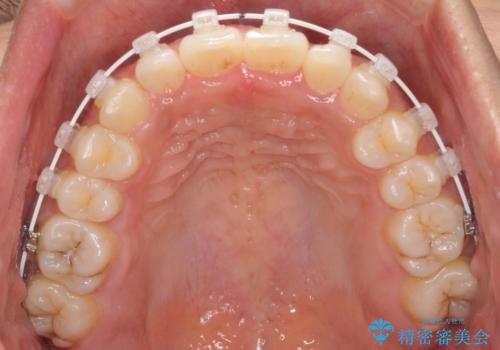

インビザラインが続けられない ワイヤー装置での矯正治療

当初はインビザラインにて治療を開始しましたが、自己管理による治療が難しくなり、ワイヤー矯正へ転換して継続しました。

2年ほどインビザライン矯正を続けましたが、終了することができず、ワイヤーへ転換後は1年弱で終えることができました。